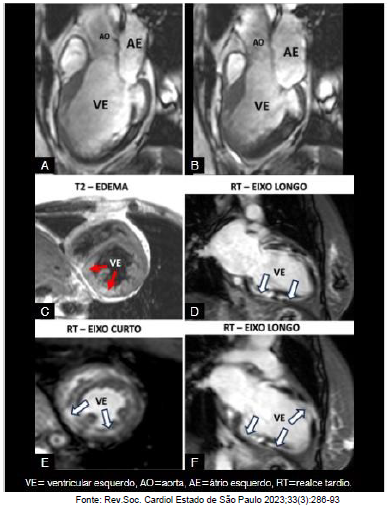

Paciente, 53 anos, sexo feminino, não hipertensa, não diabética, não tabagista, evoluindo com quadro de insuficiência cardíaca, do tipo restritiva de difícil controle, encaminhada para implante de marcapasso, devido a um Bloqueio atrioventricular (BAVT). Trouxe uma radiografia de tórax com micronódulos pulmonares difusos e um ecocardiograma feito no interior que mostrava uma miocardiopatia dilatada com FE=38%, com alterações segmentares de contratilidade. Cineangiocoronariografia normal. Foi solicitada a ressonância magnética cardíaca para esclarecimento diagnóstico, antes do implante do marcapasso e biópsia.

Após análise do caso clínico e da ressonância cardíaca realizada e apresentada acima, qual o diagnóstico mais provável?